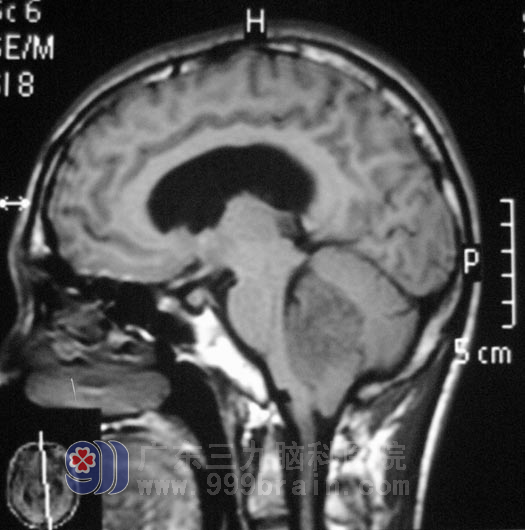

17岁的小昭,一直是健康活泼,只在入院的前一周出现头晕,伴头痛、呕吐,精神食欲差,体重下降,当地医院检查头颅CT提示:小脑占位;在广东三九脑科医院检查头颅MR提示四脑室占位伴梗阻性脑积水:http://www.999brain.com/

广东三九脑科医院综合神经外科鲁明主任告诉他们:肿瘤占位引起脑积水、颅内压力增高,引起头痛呕吐,占位效应明显,应尽早手术治疗,否则出现脑疝,后果非常严重。5月1日,鲁明主任为小昭在全麻下行右侧脑室外引流术+脑干四脑室占位切除术。显微镜下见灰白色肿瘤组织,质软,肿瘤血供丰富、包膜边界欠清晰,术中见肿瘤起源于右侧脑干背侧,充填四脑室,伸入四脑室侧孔。将肿瘤全切后,经过精心的治疗护理,小昭已经出院回家休养。术后病理检查结果为:髓母细胞瘤,WHO IV级。

髓母细胞瘤是中枢神经系统恶性程度最高的神经上皮性肿瘤之一,生长隐蔽,早期症状缺乏特征,常被病人亲属和医生所忽略,首发症状为头痛、呕吐等,多数患者因四脑室梗阻产生颅内压增高而出现呕吐,头痛症状加重才就诊。髓母细胞瘤一般多发生于学龄前或学龄期儿童尤其是男孩。http://www.999brain.com/